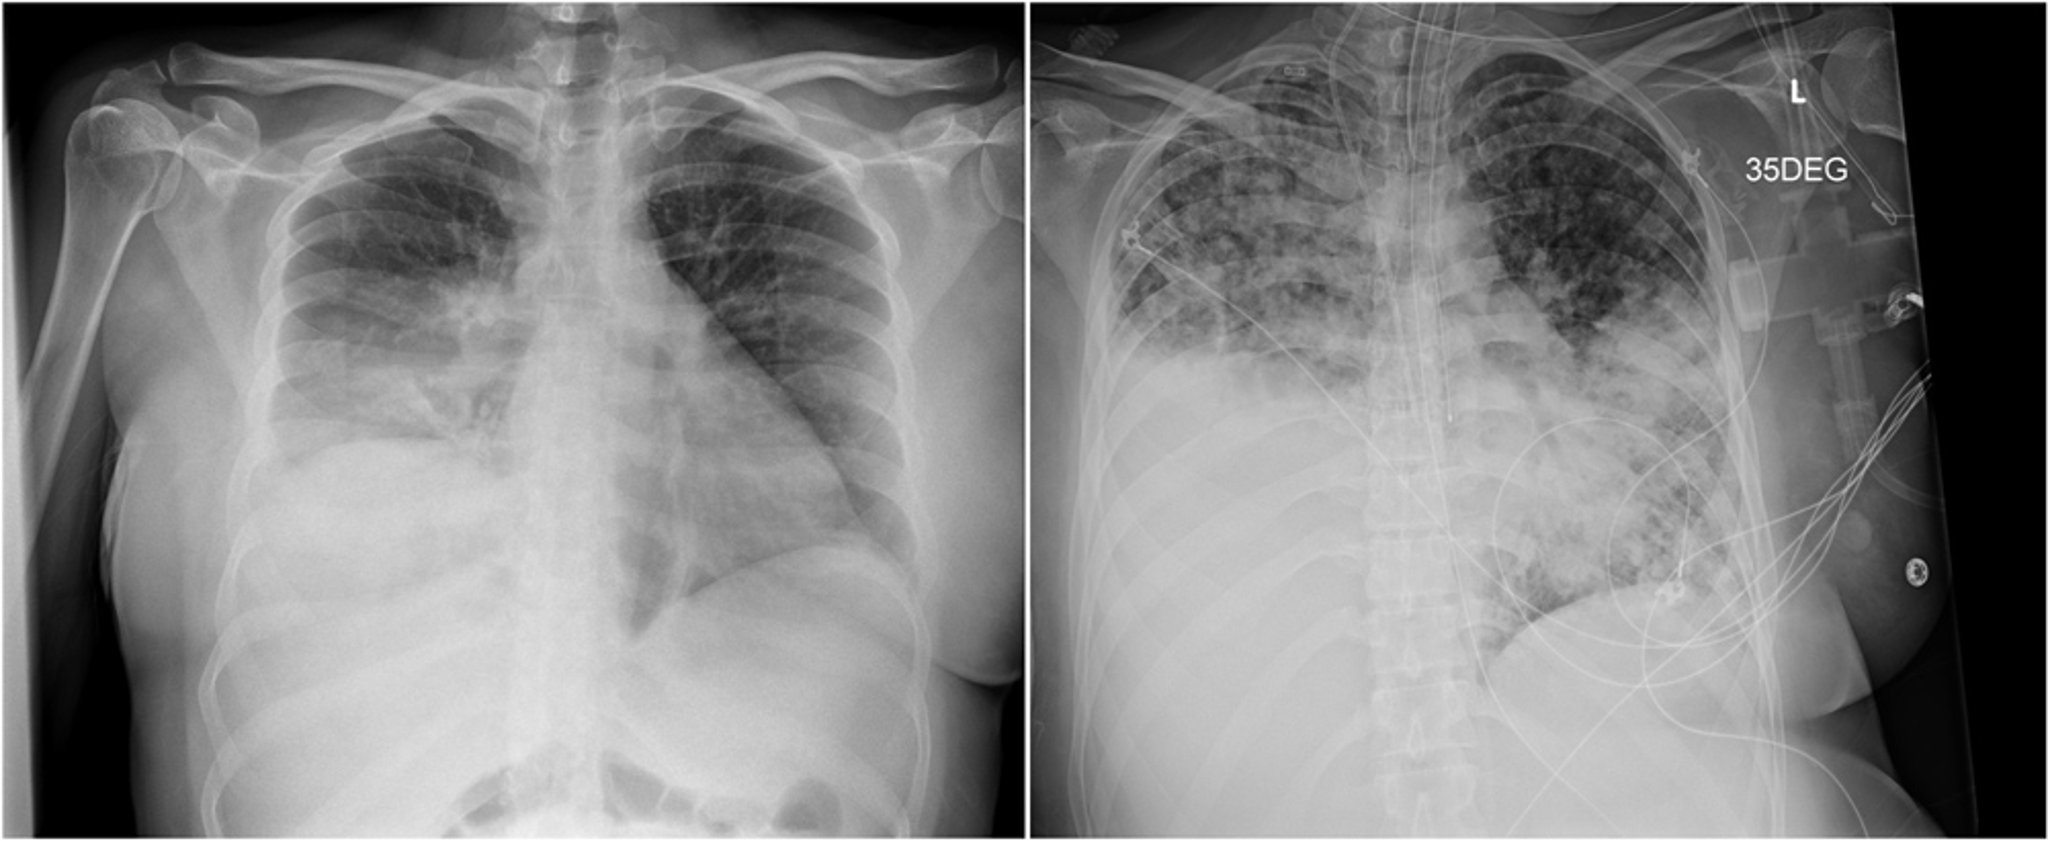

X-quang bên trái cho thấy đông đặc thùy dưới bên phải bị nhầm lẫn với viêm phổi do vi khuẩn. Chụp X-quang bên phải, chụp ba tuần sau, cho thấy bệnh tiến triển với các đám mờ vùng khí đạo hai bên và đông đặc ở phổi dưới bên phải.

Hình ảnh do bác sĩ, thạc sĩ Paschalis Vergidis.